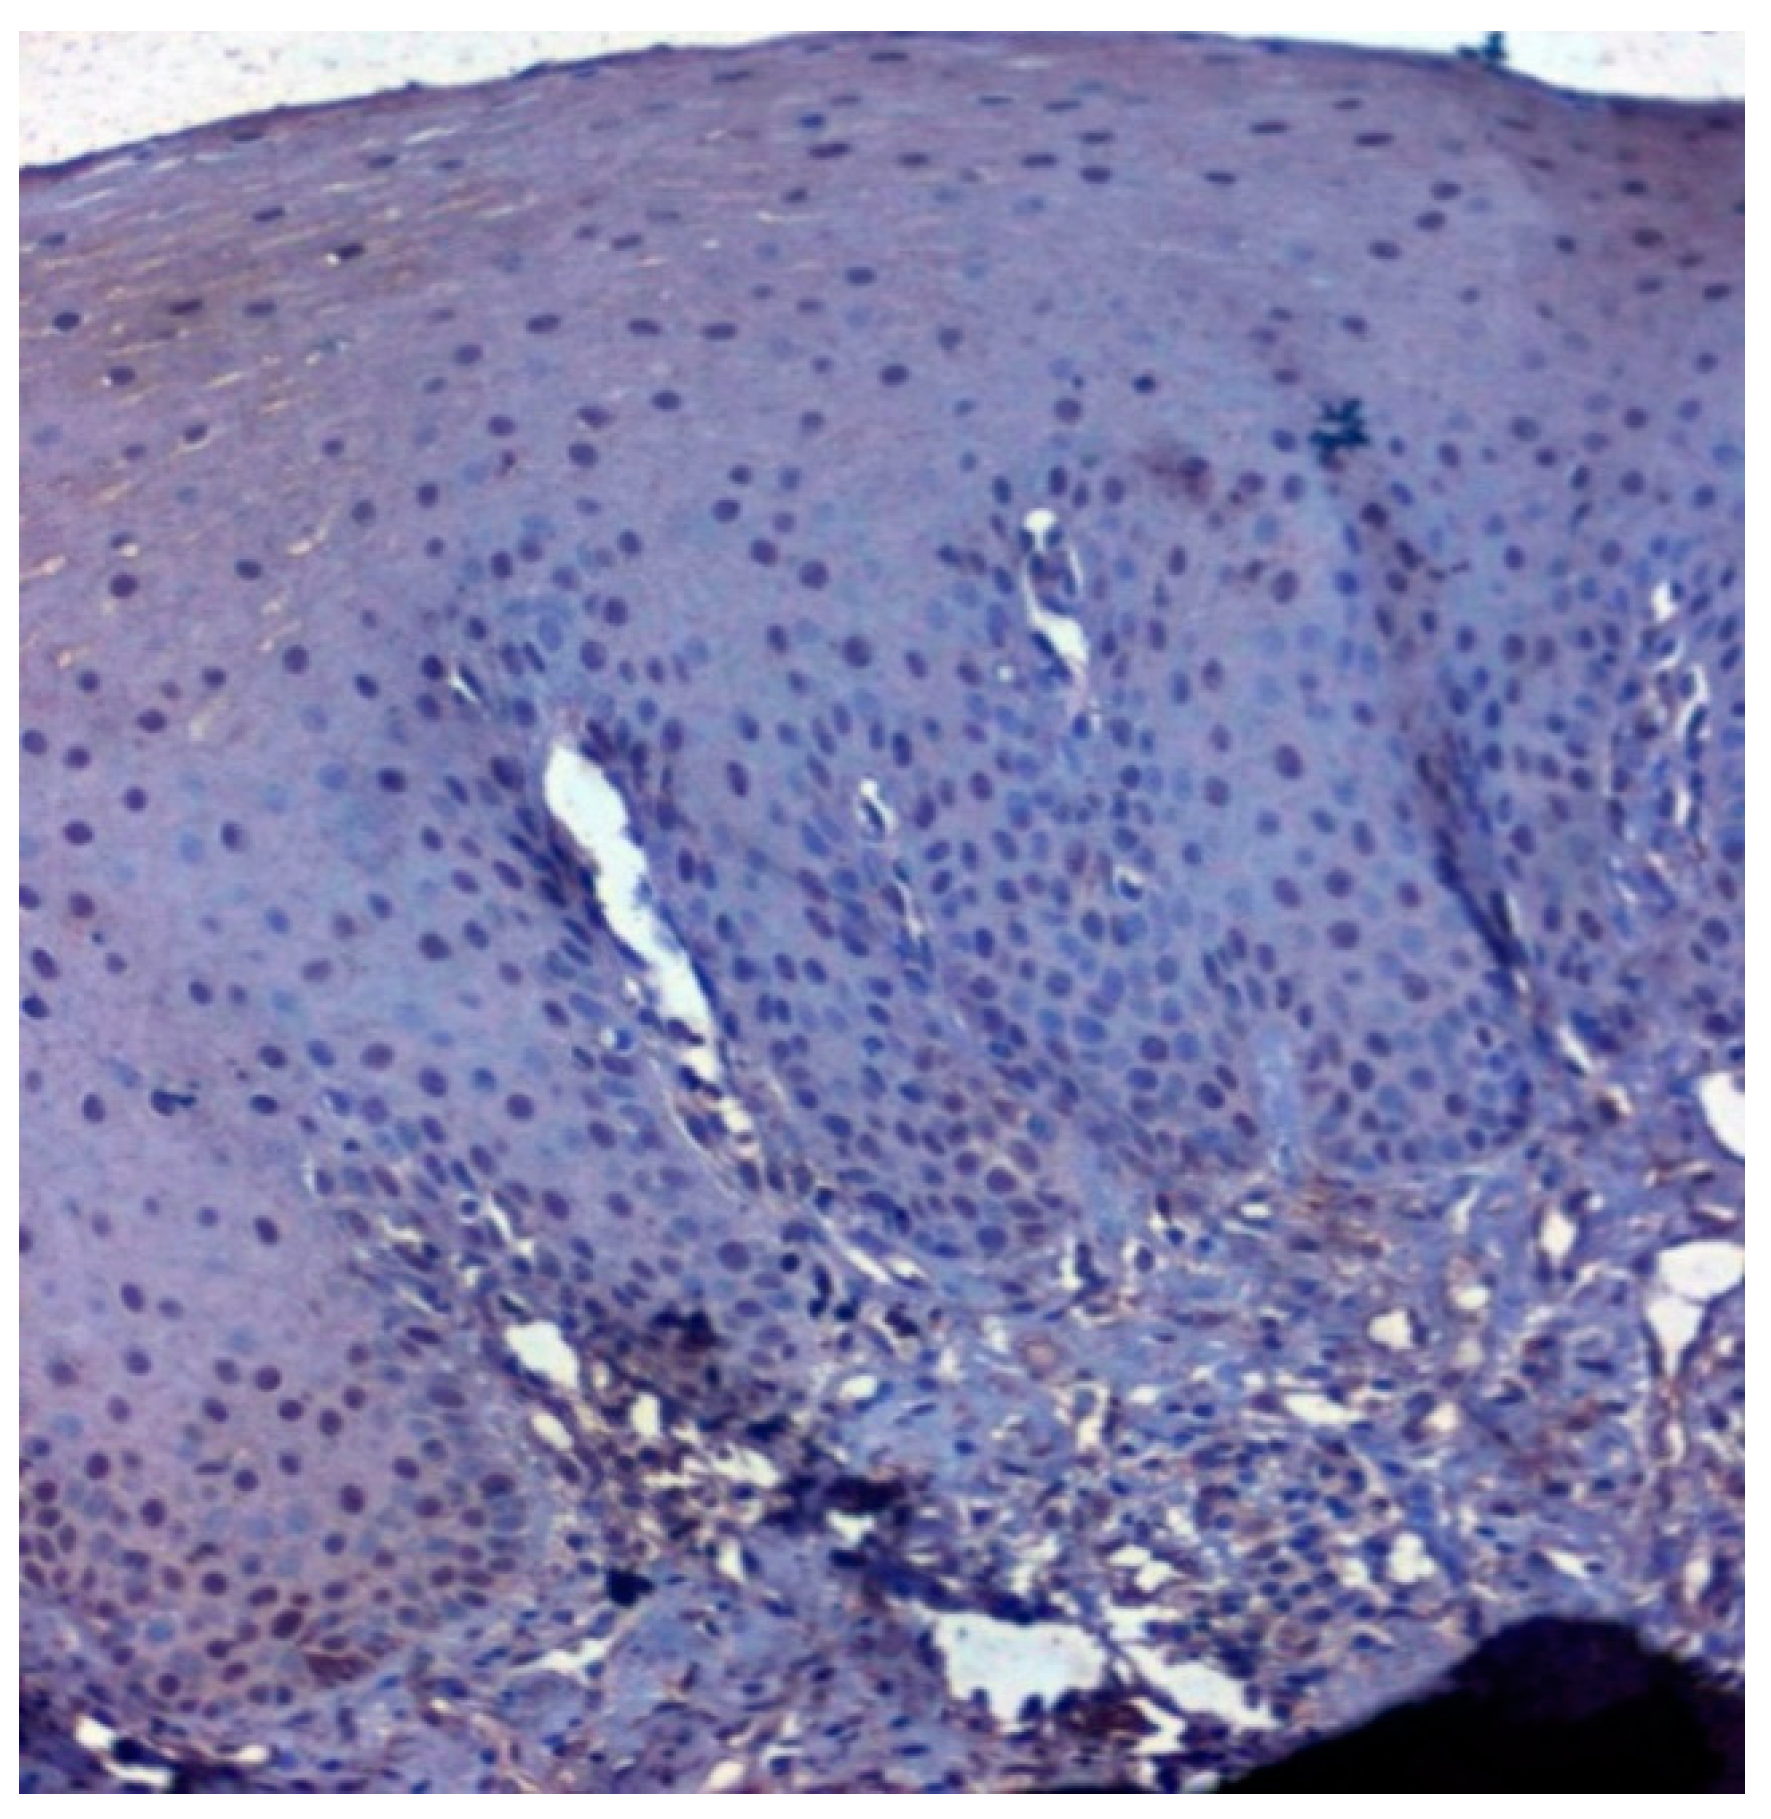

The expression of HSP 70 was studied in 117 patients, of which positive immunoexpression was found in 69.2% (81/117) patients. HSP overexpression was increased in OSCC oral cancer and OSMF compared to normal (p = 0.012; χ2 = 8.805). HSP overexpression significantly correlated (p = 0.016; χ2 = 6.705) with increased age (>47 years). HSP overexpression also showed a significant correlation with epithelial abnormality with increasing grades of dedifferentiation (p = 0.05; χ2 = 9.313) (Table 5). Figure 10 shows the expression of HSP 70 in normal oral samples showing negative epithelial cells. Figure 11 shows an expression of HSP 70 in OSMF samples showing intense cytoplasmic and nuclear positivity. Figure 12 shows the expression of HSP 70 in OSCC samples showing intense cytoplasmic and nuclear positivity.

Figure 10.

IHC for HSP 70 in normal samples (under 20× magnification).

Figure 11.

IHC for HSP 70 in OSMF samples (under 20× magnification).